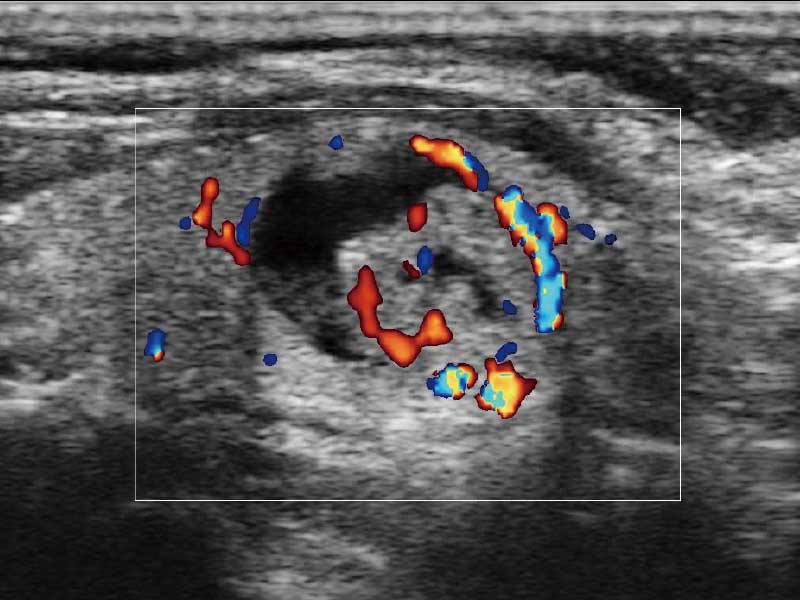

E2便携式彩色多普勒超声诊断系统采用专业的超声技术平台、高度集成化的硬件模块和结构设计、简便的操作流程、多探头接口设计,兼顾了优质图像、轻便机身以及台便两用的临床使用需求。

• 高端成像技术

μ-Scan微米成像、空间复合成像、高分辨率血流成像。

临床图